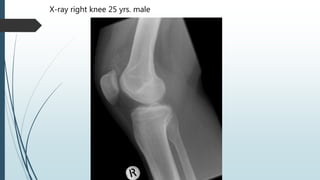

X-ray right knee 25 yrs. male

Extensively calcified

synovial sarcoma in a 36-

year-old woman